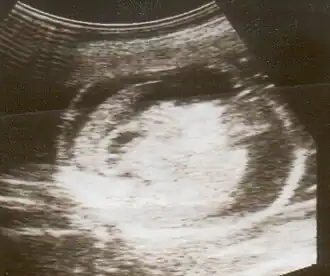

| Uma ultrassonografia mostrando um feto com hidropisia fetal. | |

Hidropisia fetal pode ser diagnosticada e monitorada por ultrassom. O exame Pré-natal e a ultrassonografia permitem a identificação precoce de hidropisia fetal.